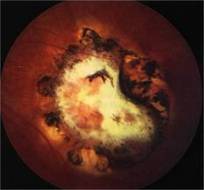

TOXOPLASMOSIS |

Toxoplasmosis is a disease provoked by the obligate intracellular protozoan Toxoplasma gondii. It is found in a variety of mammal and bird hosts. The most common intermediate host is the cat. It is one of the most frequent causes of retinochoroiditis in humans, with more than 60 percent of the United States population and up to 75 percent of the world's general population possessing some seropositive findings Etiology

Ophthalmic Features